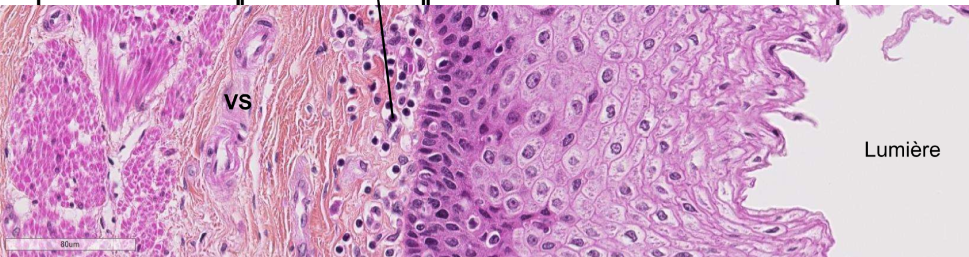

On regarde quelle lame, indique les fleches

lame de la trachée,en HES, on regarde ici la muqueuse

La muqueuse est composé du chorion (vs et tissus conjonctifs) et de l’épithélium de revêtement (respiratoire)

donne les caractéristiques de l’épithélium de reveptement respiratoire de la tracheé

cellules cylindriques, pseudostratifié, cilié, qui présente une membrane basale